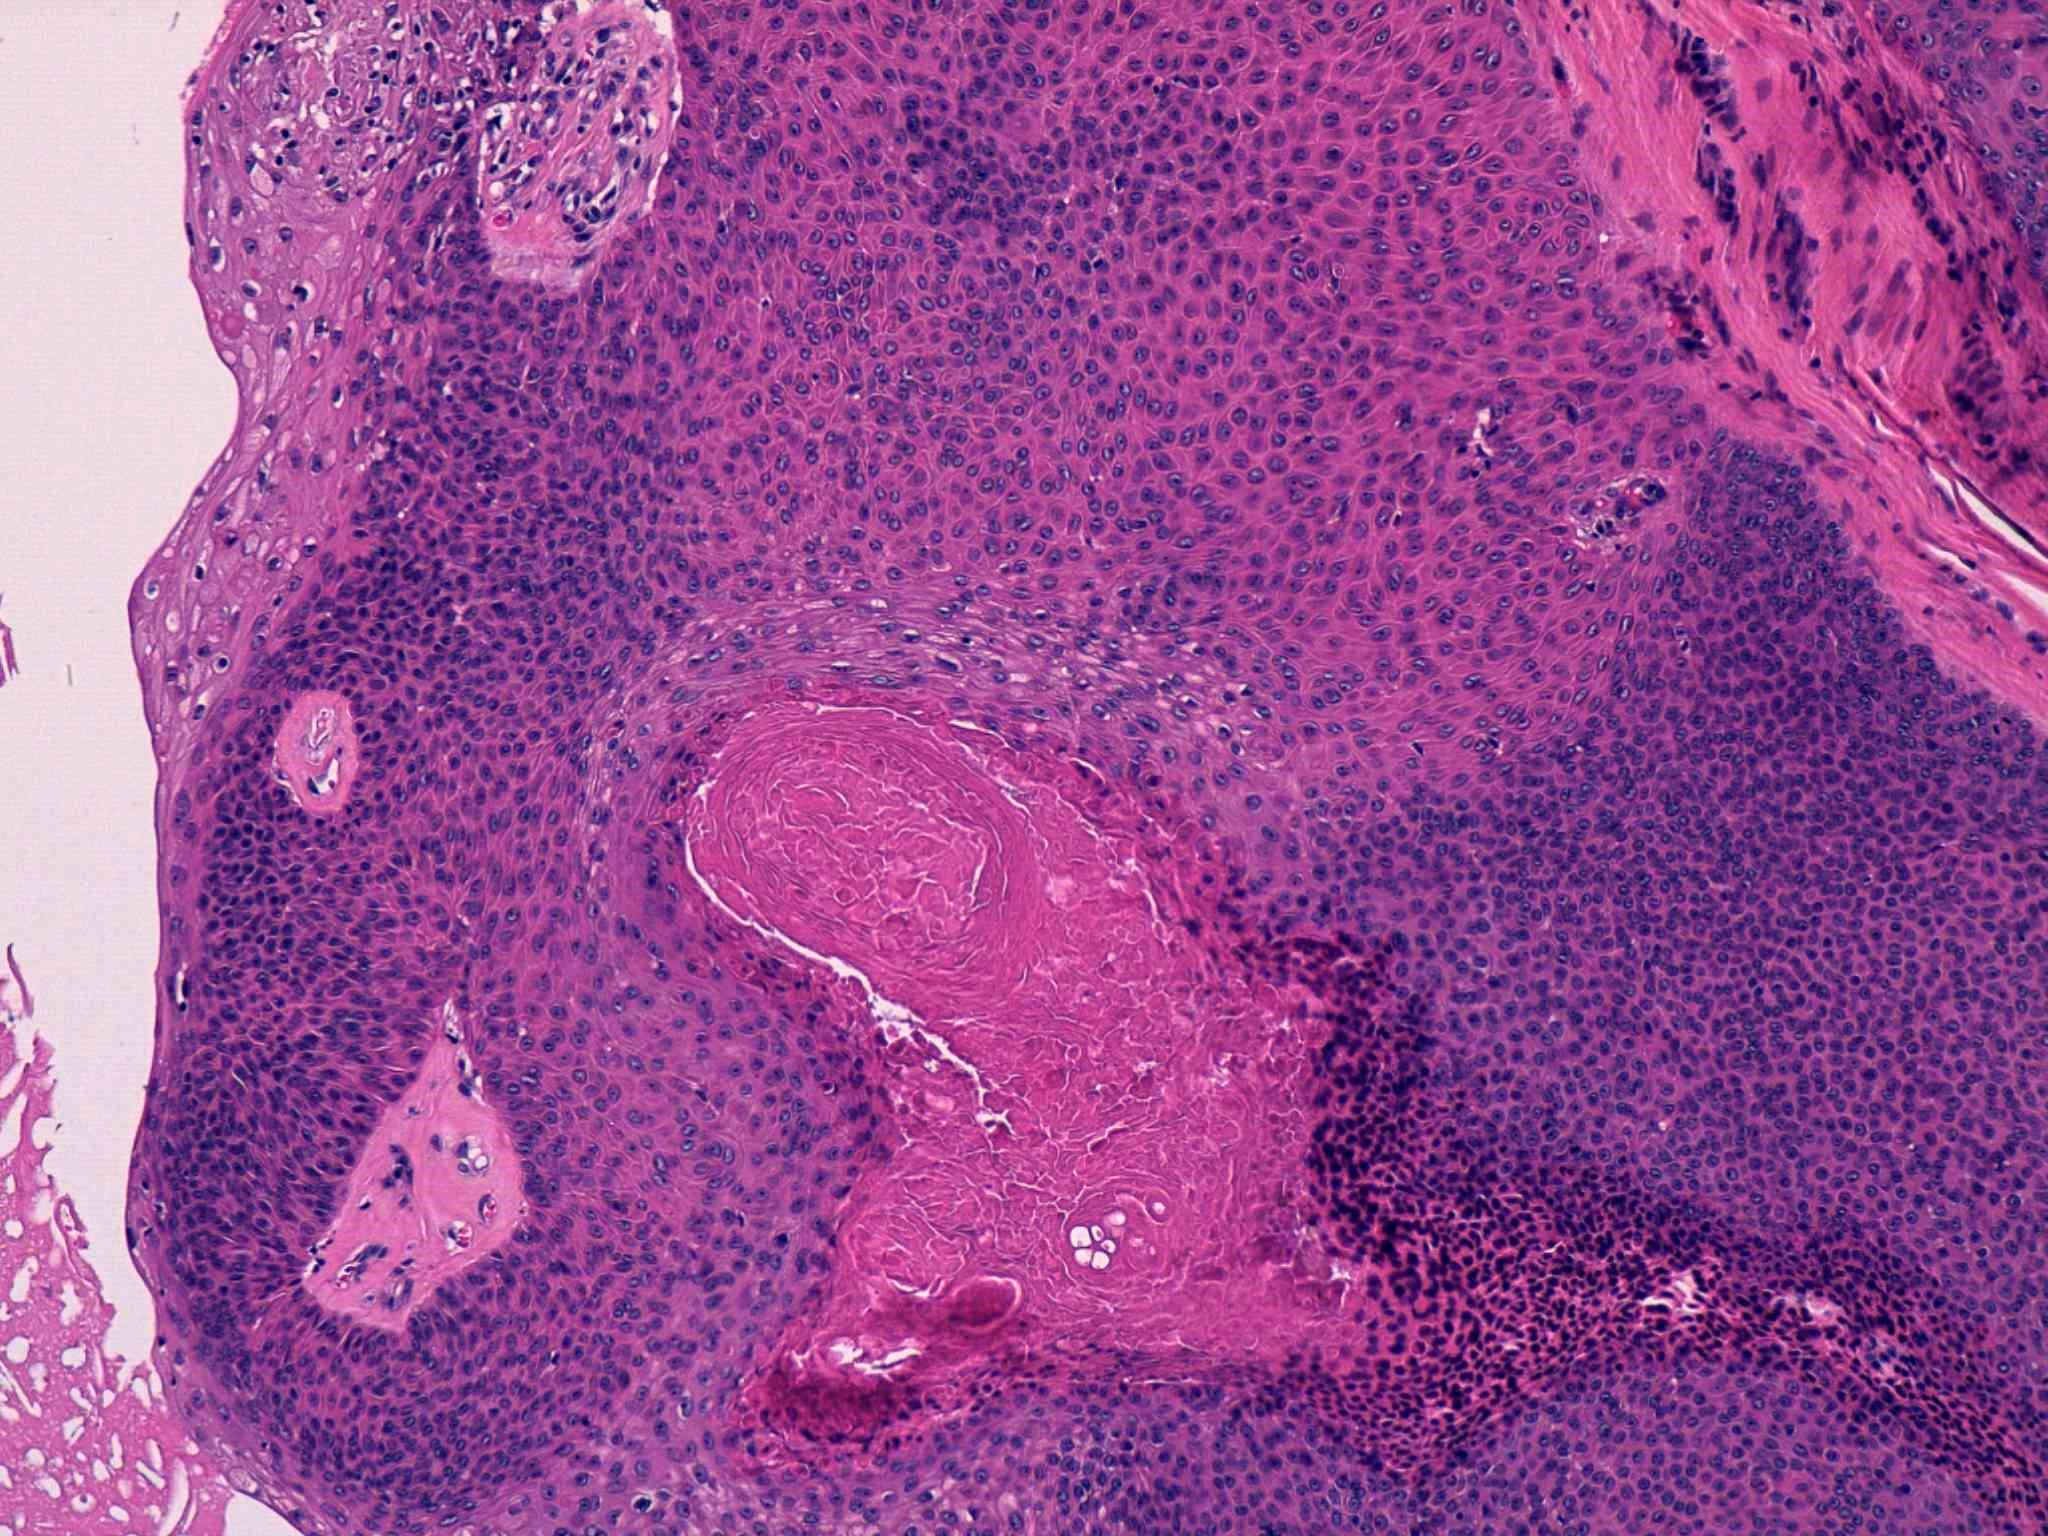

28 -- image_2011y10m04d_15h39m21s.jpg